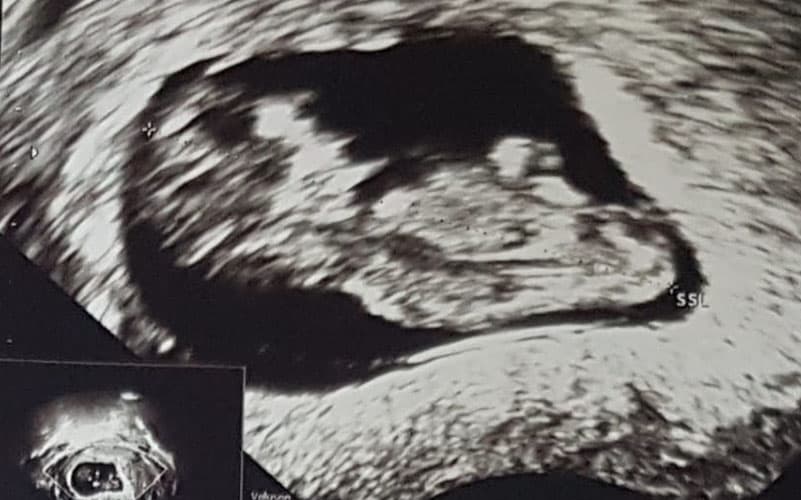

Ultraschallbilder aus dem 2. Trimester (13. bis 28. SSW)

Im 2. Trimester bekommt man oft die schönsten "Ganz-Körper" Ultraschallbilder. Das Baby ist nun so groß, dass man alles gut erkennen kann und noch nicht zu groß, so dass es noch ganz auf das Bild passt. In dieser Zeit lässt sich meist das Geschlecht bestimmen, wobei manche Babys es einfach nicht preis geben wollen und sich immer so drehen, dass man nichts erkennen kann.